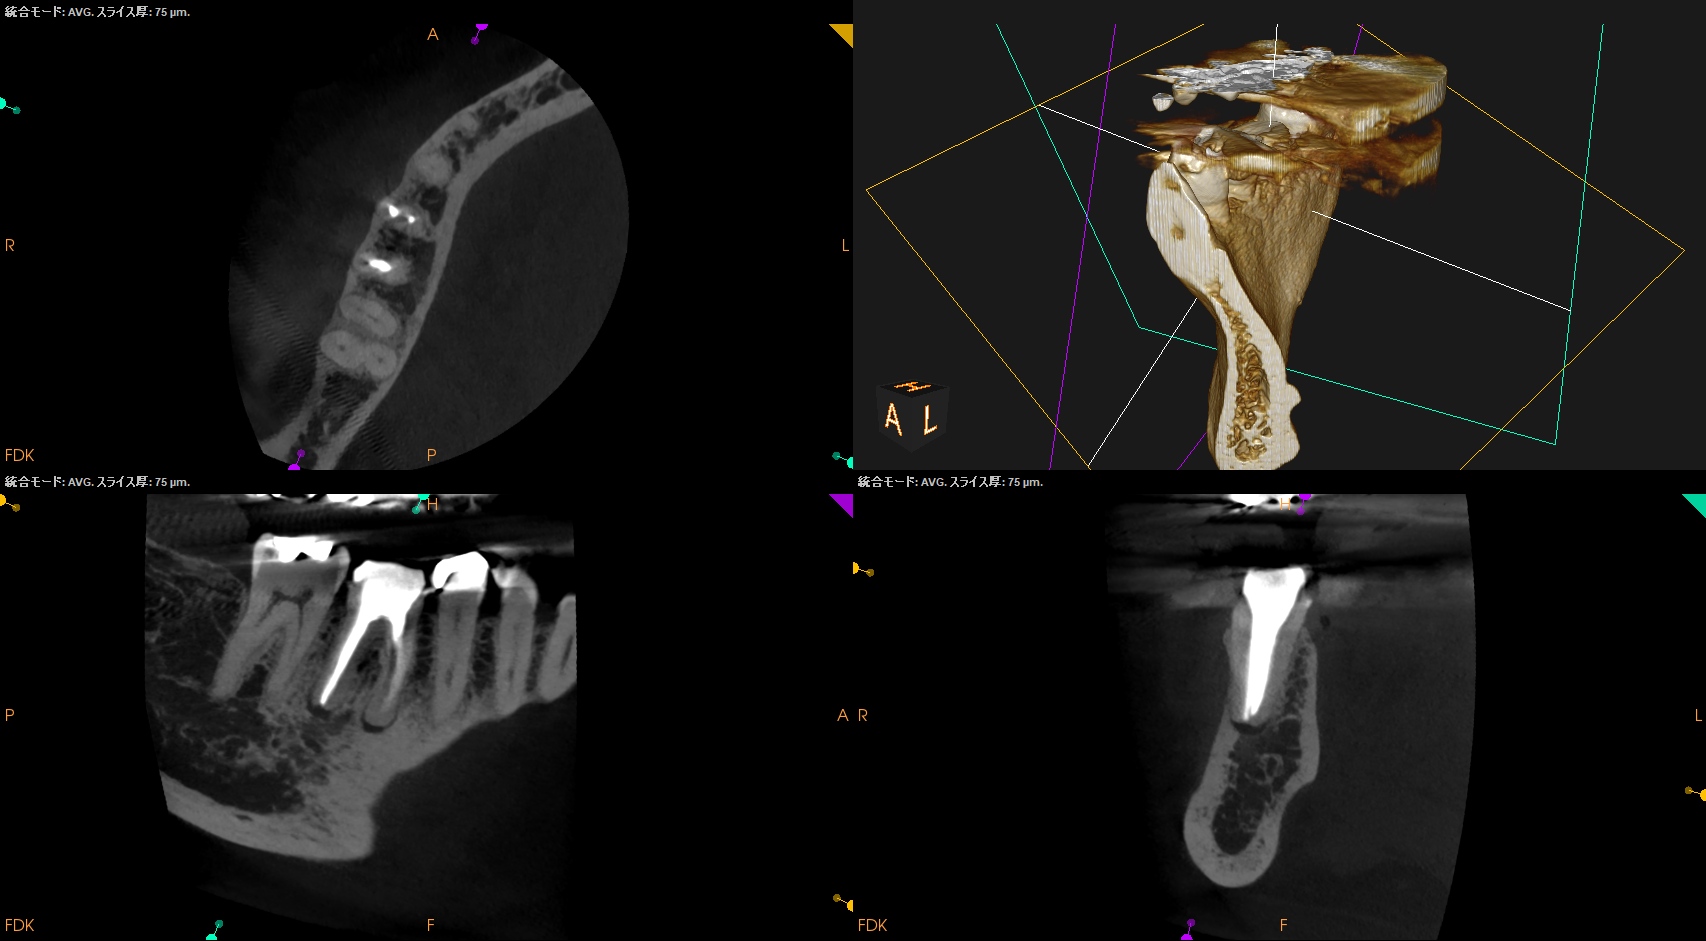

CBCT(2025.12.2)

M,Dの根尖部には病変がある。

またMもDも形成・根充が太くなされているので治療は成功率が低いであろう再根管治療ではなくApicoectomyだ。

MのApexの位置をCBCTを参考に予想し、Osteotomyをする。

DのApexの位置をCBCTを参考に予想し、OsteotomyしRoot resectionした。